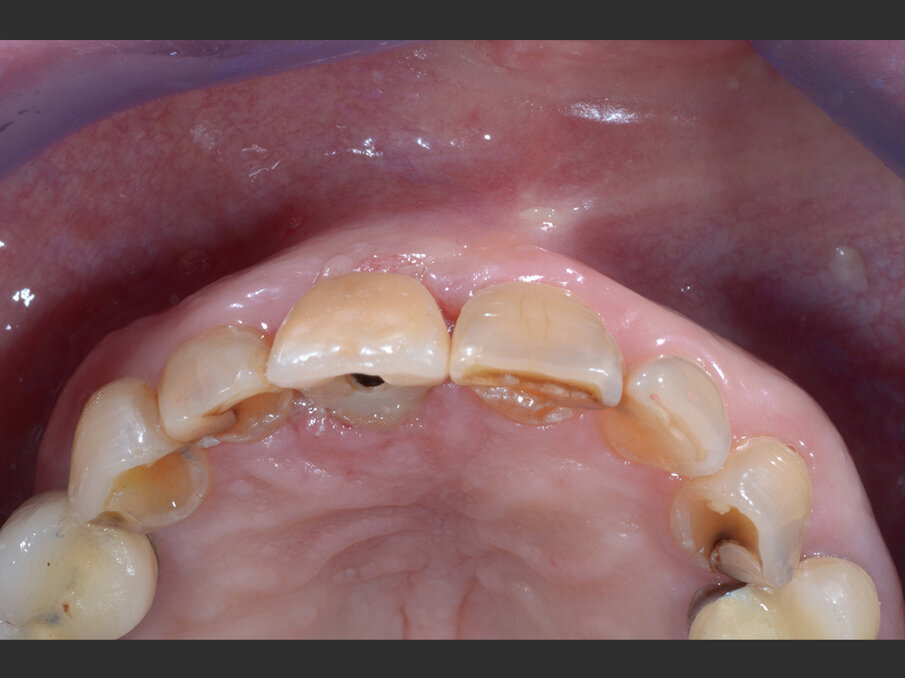

La paziente, donna di 60 anni, non fumatrice ed in buone condizioni di salute generale, si presenta in studio con sintomi di pulpite irreversibile a carico dell’elemento 1.1. L’esame clinico (Figg. 1a, 1b) e radiografico (Fig. 2a) confermano la presenza di una lesione cariosa radicolare che ha colpito il versante mesiale.

Fig. 1a - Valutazione pre-operatoria - visione frontale: l’elemento 1.1 è sintomatico e mostra segni e sintomi di pulpite irreversibile.

Fig. 1b - Valutazione pre-operatoria - visione palatina: è possibile apprezzare la lesione cariosa corono-radicolare.